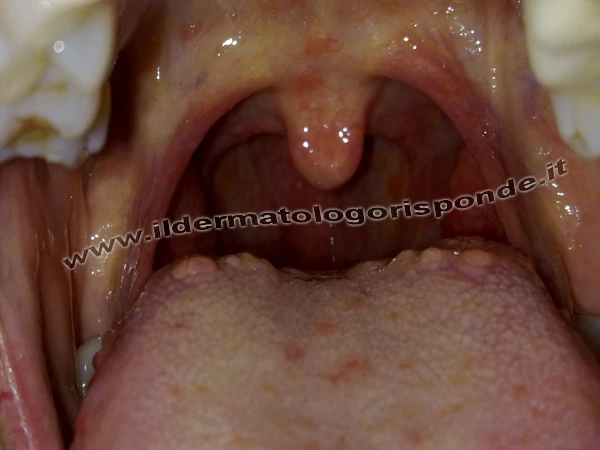

Lingua nigra villosa (foto in alto) e ipertrofia delle papille circumvallate (foto in basso)

Tra le glossopatie parafisiologiche ricordiamo la lingua a carta geografica (secondo recenti studi, espressione della psoriasi del cavo orale), la lingua nigra villosa (allungamento e pigmentazione delle papille filiformi), la glossite romboidale mediana di Brocq e Pautrier (chiazza eritematosa depressa e infiltrata), la lingua scrotale o plicata (talora associata alla sindrome di Melkersson Rosenthal), la papillite linguale transiente e la papulosi linguale cronica. In alcune situazioni fisiologiche si può verificare un’ipertrofia delle papille circumvallate che si presentano come piccole protuberanze disposte lungo la V linguale (solco naturale a forma di V rovesciata localizzato sul dorso della lingua).

Ipertrofia delle papille cirumvallate della lingua